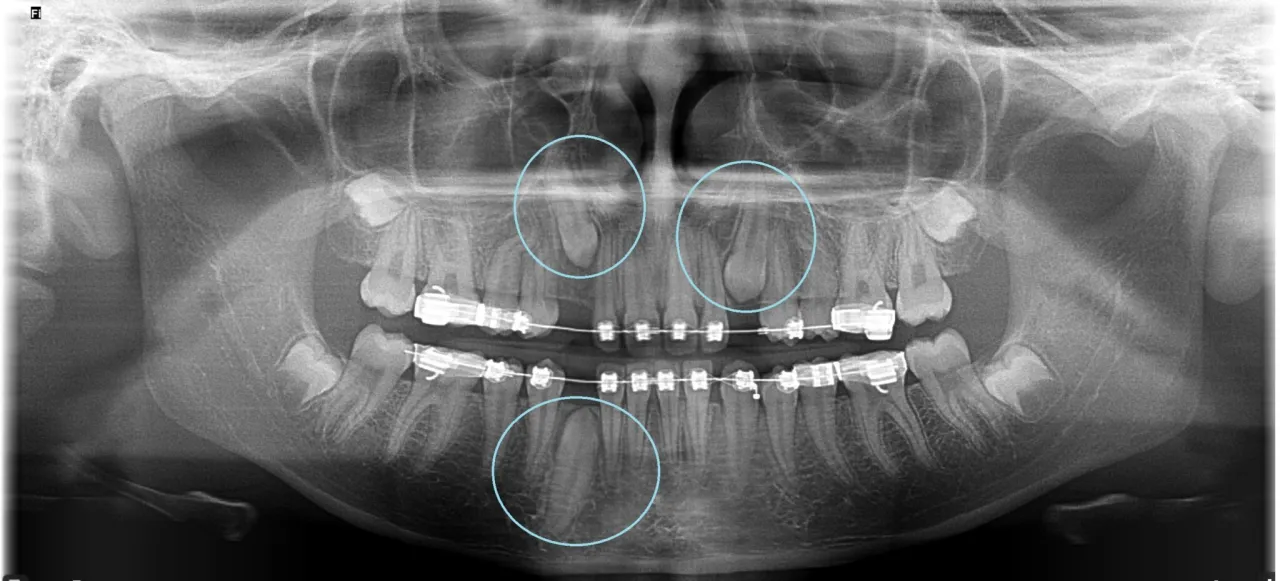

Ząb zatrzymany to taki, który mimo prawidłowego rozwoju nie wyrznął się w odpowiednim czasie i pozostaje ukryty w kości szczęki lub żuchwy. Najczęściej dotyczy to kłów, zwłaszcza w podniebieniu, oraz zębów mądrości, czyli ósemek. Jego odsłonięcie jest często niezbędne, szczególnie w kontekście leczenia ortodontycznego. Celem jest wprowadzenie tego zęba do łuku zębowego, co ma kluczowe znaczenie dla prawidłowego zgryzu, funkcji żucia oraz, co równie ważne, dla estetyki uśmiechu. Bez tej interwencji ząb zatrzymany może prowadzić do wielu problemów, takich jak przemieszczanie się sąsiednich zębów, uszkodzenia korzeni, a nawet powstawanie torbieli.

Zanim przystąpimy do zabiegu, kluczowe jest odpowiednie przygotowanie. Zawsze zaczynamy od dokładnej diagnostyki, która obejmuje zazwyczaj zdjęcia rentgenowskie, takie jak pantomogram czy tomografia komputerowa. Dzięki nim mogę precyzyjnie ocenić położenie zęba zatrzymanego, jego relacje z sąsiednimi strukturami i zaplanować optymalny przebieg interwencji. Pacjent powinien wiedzieć, że te badania są niezbędne dla jego bezpieczeństwa i skuteczności leczenia. Na podstawie diagnostyki omawiam z pacjentem cały plan leczenia, odpowiadając na wszelkie pytania.Nacięcie dziąsła i odsłonięcie korony: co dokładnie robi chirurg?

Po odsłonięciu korony zęba następuje kluczowy etap: przyklejenie do niej specjalnego zamka lub guzika ortodontycznego. Ten mały element jest wyposażony w delikatny łańcuszek, który będzie później wykorzystany przez ortodontę. Jego zadaniem jest stopniowe i kontrolowane przesuwanie zęba zatrzymanego do właściwej pozycji w łuku zębowym. To właśnie dzięki temu ząb, który wcześniej nie mógł się wyrznąć, zostanie wprowadzony do zgryzu.

Odsłonięcie zęba zatrzymanego to często pierwszy, ale niezwykle ważny etap w kompleksowym leczeniu ortodontycznym. Dzięki tej procedurze ortodonta zyskuje możliwość podłączenia zęba do aparatu i stopniowego, kontrolowanego przesuwania go do właściwej pozycji w łuku zębowym. To pozwala na pełne wykorzystanie potencjału naturalnego uzębienia pacjenta i uniknięcie konieczności ekstrakcji innych zębów.